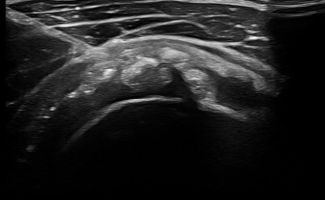

- Calcification stage: In this stage, calcifications are compact and hard, causing mild, chronic pain.

- Resorption stage: Calcifications become fluid and have a soft consistency, similar to toothpaste. In this stage, calcific tendonitis is very painful. Common symptoms include difficulty in moving the arm and intense pain that can radiate to the elbow and/or neck.